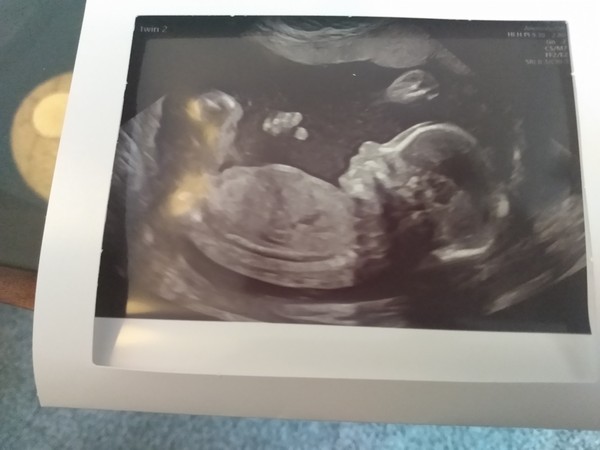

I'll upload a photo from mine on Tuesday at some point, got a good un of twin 2, twin 1 is useless 😆

Here's a photo from my scan Tuesday of twin 2, we've given up on seeing twin 1 resembling anything human until the birth 😆

👣 Due Nov/Dec 👣 it's the 20 week scans! 👣

@champoopapi such a cute pic! Do they know which is twin 1 & 2 the whole way through or do they swap about if you get what I mean?